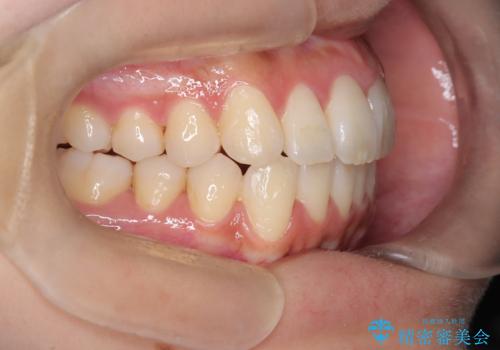

前歯の叢生・Ⅱ級咬合を改善|TADを用いた遠心移動+インビザライン矯正

- 前歯のガタガタと臼歯関係のⅡ級(上顎の歯列が前方にある状態)を改善するため、TAD(歯科矯正用アンカースクリュー)を使用したインビザライン矯正を計画しました。まずTADを上顎の適切な位置に設置し、それを固定源にして奥歯を後方(遠心)へ移動させ、十分なスペースを確保します。その後、インビザラインによるマウスピース矯正で前歯の歯列を整え、臼歯関係を正常化します。治療期間はおよそ1年半〜2年を想定しています。

前歯部の叢生(ガタガタ)と臼歯関係のズレを改善するため、抜歯をせずに奥歯を後方へ移動(遠心移動)させることを選択しました。TADという小型のアンカースクリューを顎骨に設置することで、確実かつ効率的に奥歯を後方へ移動させました。併せて透明で目立ちにくいインビザラインを用いることで、審美性を保ちながら治療を進めることが可能でした。患者様の負担が少ないマウスピース矯正と固定源のTADを組み合わせることで、抜歯することなく歯並びと噛み合わせを大幅に改善でき、大変ご満足いただけました。